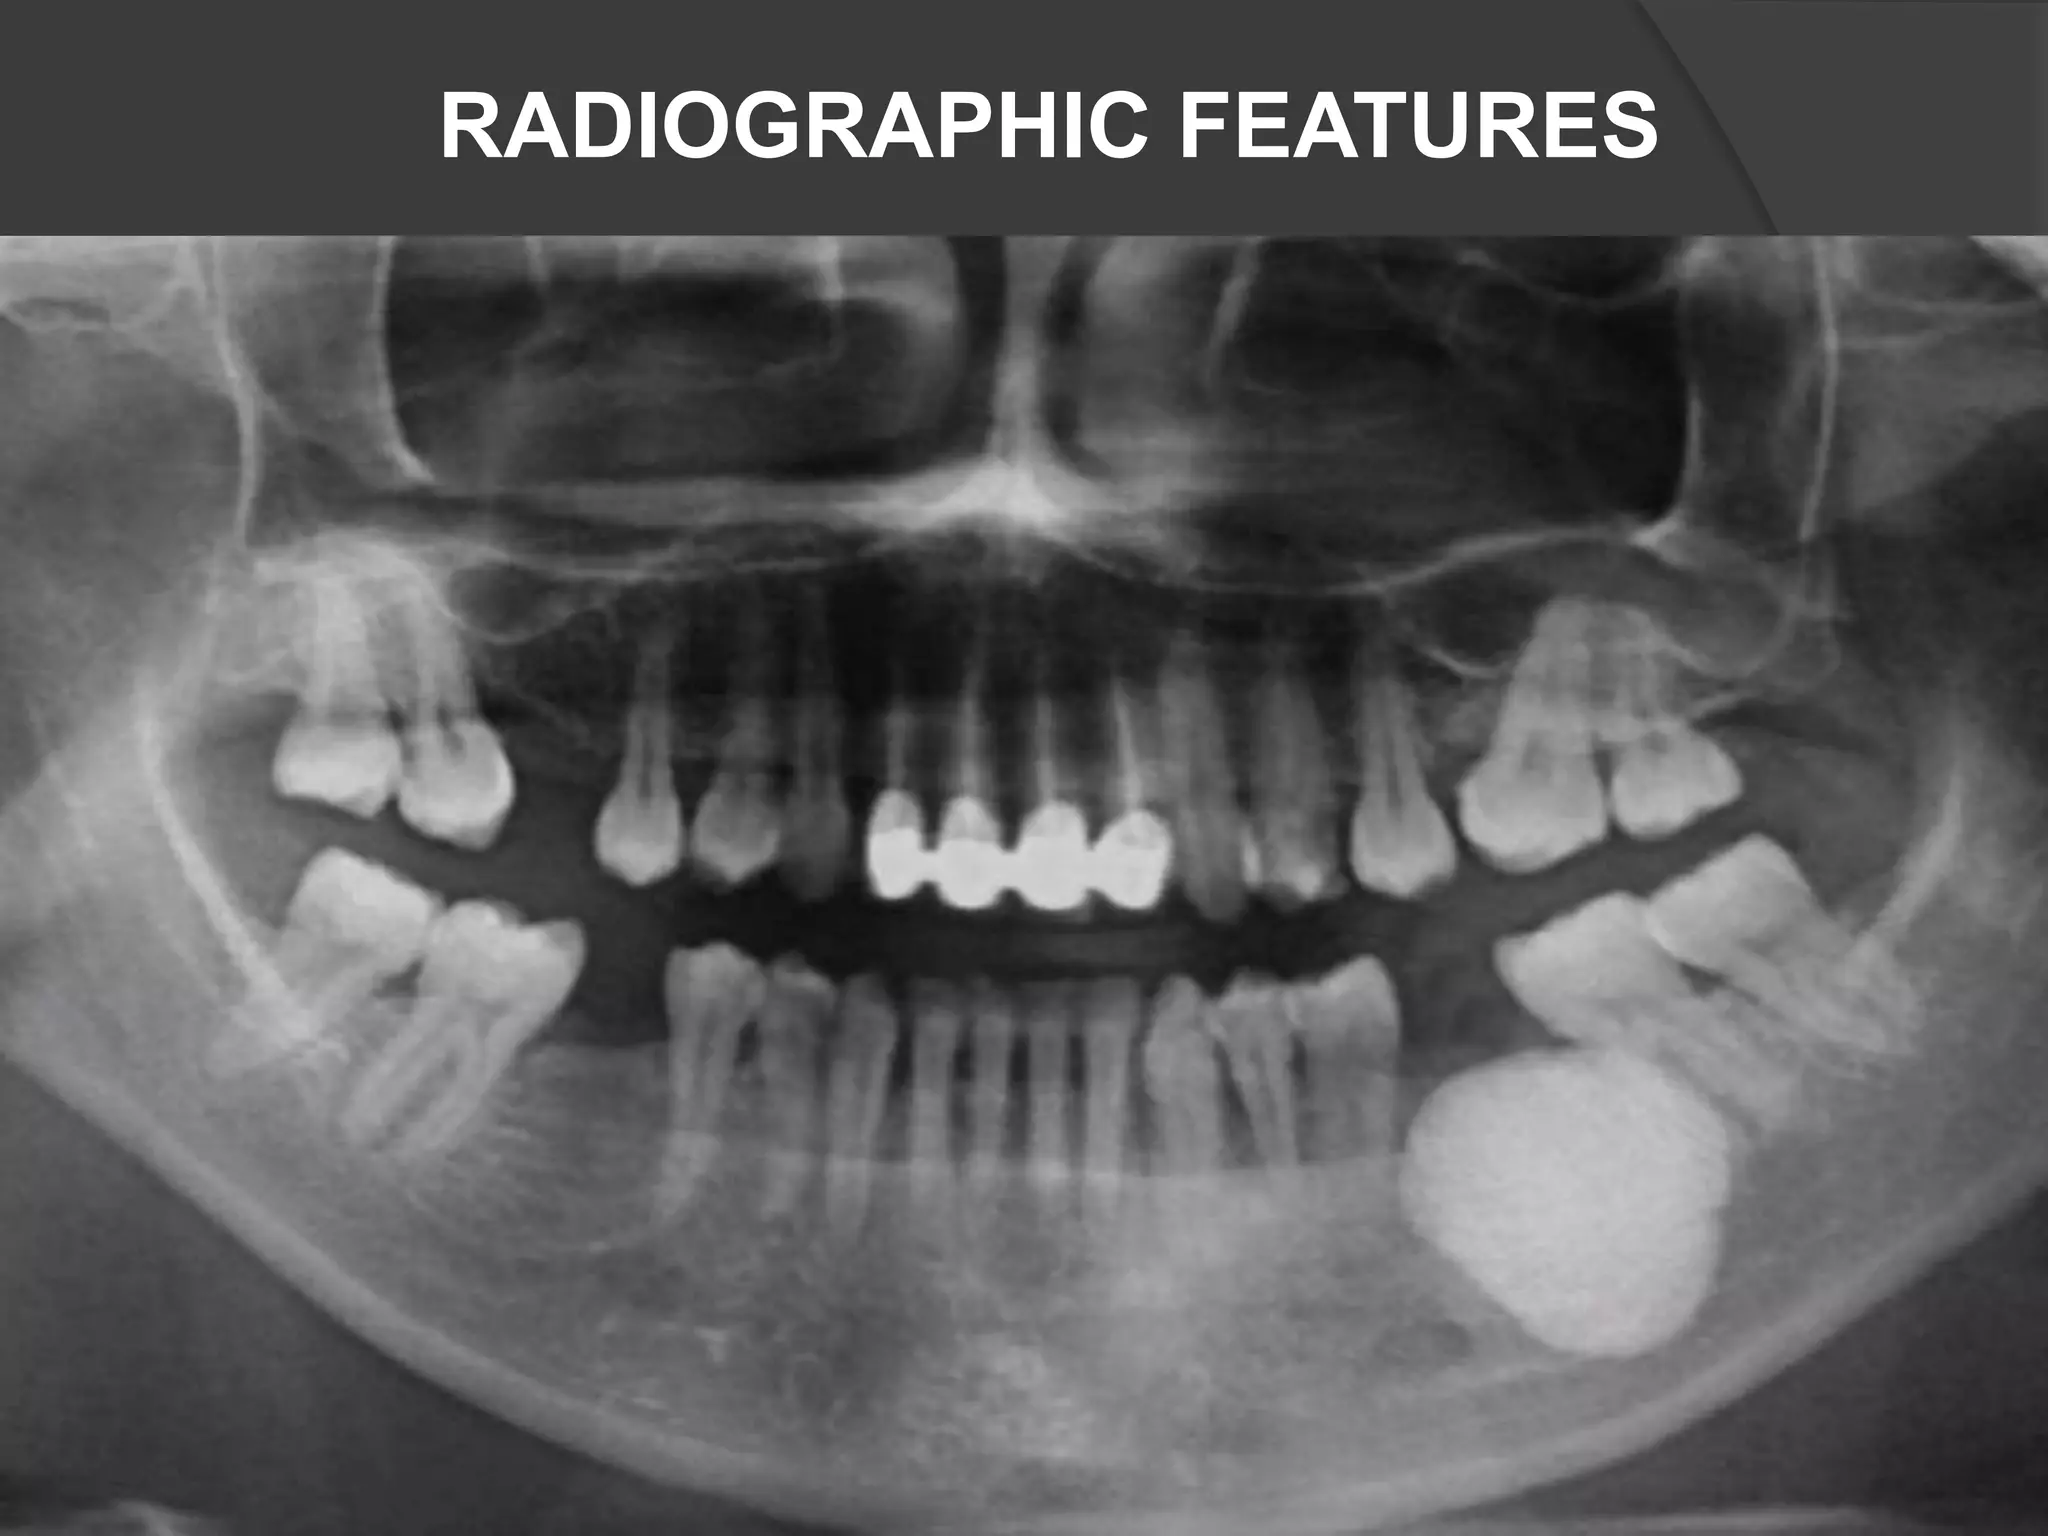

• #34 (a) The arrow shows the lytic lesion in the body of right mandible with floating teeth (orthopantomograph). (b) The arrow shows the lytic lesion in right mandible (contrast enhanced computed tomography mandible)

• #35 Initial panoramic radiograph showing a radiolucent lesion with a moth-eaten margin in the right mandible. The lesion resulted in the fracture of the mandible. The involved teeth appear to be floating on the lesion.